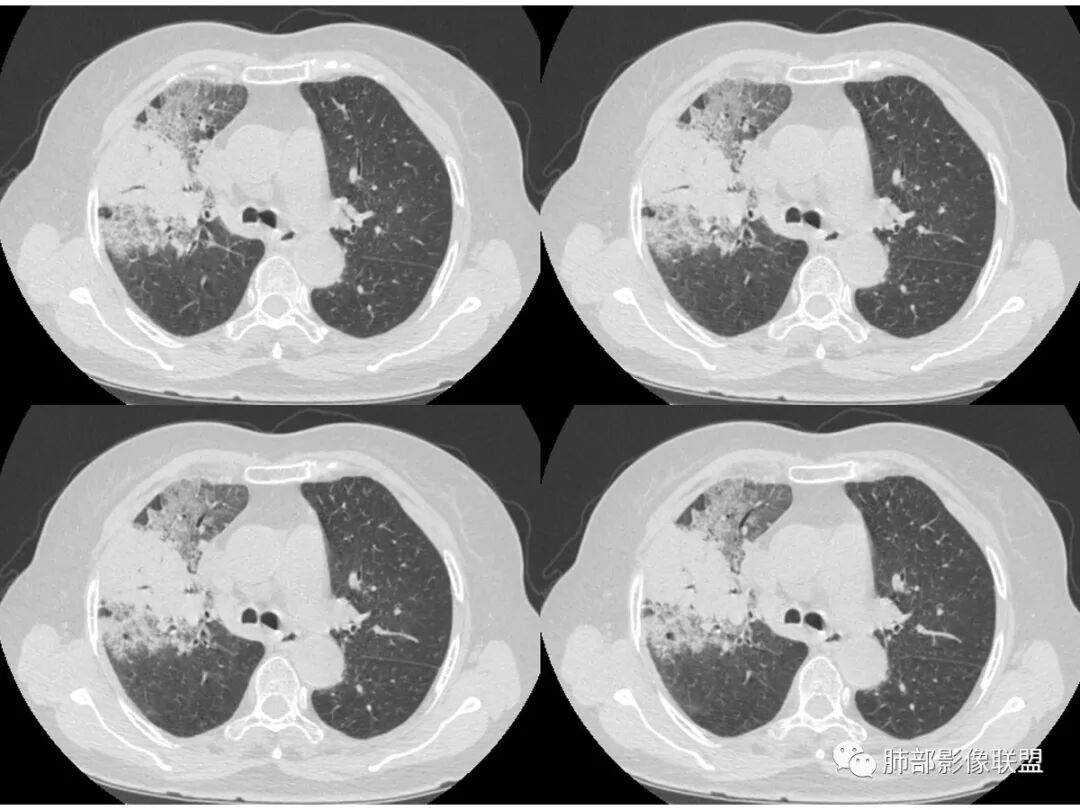

右肺上叶大片状阴影,内见僵硬的支气管,部分支气管轻度扩张,内见一空洞和液平,病灶边缘可见磨玻璃影,首先考虑恶性病变,粘液性腺癌伴感染可能。

老年女性,右肺上叶大片实变及磨玻璃密度影,磨玻璃边缘清晰,内可见小叶间隔增厚,内可见空洞,似可见分隔,叶间裂局部膨隆,纵膈窗,没有增强,枯树枝不明显,肺炎型肺癌可能,鉴别大叶性肺炎,结核?

胸CT:右肺上叶实变内可见支气管充气征,近端支气管狭窄,远端扩张,周围可见毛玻璃影,右肺中叶支气管闭塞,并可见气道壁钙化,右肺中叶体积缩小,实变内可见空洞,并可见气液平面,空洞周围可见毛玻璃样影,右肺下叶支气管开口狭窄,右肺门淋巴结肿大。纵隔窗可见病灶与壁层胸膜间隙增宽,考虑良性病变-----感染性病变------TB?

老年女性,右肺中上叶病灶,血象不高,血沉高,TB dna阴性,上叶尖端病灶,紧贴胸膜,边界似清非清,中间可见实变,内见枯树枝征,首先考虑粘液腺癌可能性大。患者右肺中叶见空洞、气液平,病灶没多发空洞,可见气液平,考虑合并TB感染。

老年女性,无诱因咳嗽咳痰,白色粘液痰,抗炎治疗无好转,右肺多叶磨玻璃影,其内见枯树枝征,磨玻璃边界清,中间见实变影,且部分实变影内见空洞或局部支气管扩张,内壁光整,无纵隔淋巴结肿大,常规考虑粘液性腺癌,感染性病变待排,细菌性的排除,白细胞不高,不太支持,建议支气管镜检。

1.右上肺大片状影,周围有磨玻璃影,支气管截断征、枯枝征、远端支气管充气征,可见多个大小不等囊泡(支气管阻塞活瓣作用形成),病灶有少许收缩力感,叶间裂被稍牵拉内移;

病史老年女,白痰;影像实变,ggo多数边界清,病灶下缘部分不清,枯树枝,支气管近端阻塞、僵硬,病灶跨叶;病灶内空洞,有液平;间质增厚有结节感;肺炎型肺癌大于干酪性肺炎。

老年女性,慢性病程,咳嗽伴白色粘液痰,无发热腹痛,糖尿病,白细胞及C反应蛋白不高,血沉快,铁蛋白高。胸部CT,右肺上叶大片状实变伴磨玻璃密度影,边界不清,边缘局部膨隆,叶裂弧形下坠,实变影宽基底与胸膜相贴;右肺下叶前基底段见类似病灶;右肺中叶不张并空洞形成,空洞内见气液平面;综合考虑右肺上叶及下叶肺炎型肺癌,右肺中叶结核。

老年女性,病史1月,右肺上中叶大片状影,跨叶,上叶为主,磨玻璃为主,边界模糊,部分实变,内见空洞影和液气平面,壁光滑,支气管开口狭窄,局部有扩张,右肺门淋巴结钙化,首先考虑感染性病变,结核可能,鉴别粘液腺癌。

白色粘液痰,枯树枝,支气管僵直,有空洞,磨玻璃,叶间裂膨隆、下坠,吴婧老师的肺炎型粘液性腺癌十大特点中占了好多条,所以考虑粘液腺癌,就差增强看看强化如何,血管如何了

老年女性,亚急性起病,右肺上中叶大片状影,跨叶,上叶为主,磨玻璃为主,边界模糊,部分实变,内见空洞影和液气平面,壁光滑,洞内可见结节形成,局部有扩张,首先考虑感染性病变,结核可能;洞内可见结节样病灶,鉴别合并曲霉、肿瘤。

薄厚不均匀,枯树枝,支气管壁僵直,叶间裂膨隆,白色粘液痰,肿瘤标志物增高,考虑粘液肺癌可能。

患者老年女性,亚急性起病,胸部CT:右肺上叶大片实变,可内见坏死性空洞,可见mGGO,GGO边缘清晰,局部彭隆,内见支气管充气征,可惜没增强,粘液腺癌要考虑,但病灶明显是内朝外不支持,综合考虑结核,建议查痰找抗酸杆菌、气管镜

老年女性,咳白色粘液痰,右肺跨叶大片高密度影,密度不均匀,其内见支气管枯树征,有空洞,边缘部分清楚,叶间裂有下坠膨隆感。考虑粘液腺癌,鉴别干酪性肺炎